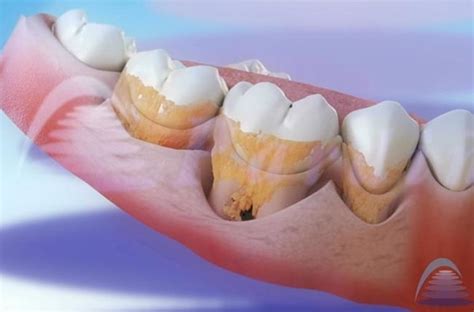

Tipos de sarro dental: supragingival y subgingival.

Dependiendo de su ubicación en la boca, el sarro se clasifica en:

- Sarro supragingival: Se encuentra en la superficie de los dientes, por encima de la línea de las encías. Es de color blanco o amarillento y suele ser más fácil de detectar y eliminar.

- Sarro subgingival: Se forma debajo de la línea de las encías y es más difícil de ver. Tiene un color oscuro debido a la acumulación de pigmentos provenientes de la sangre y bacterias. Su presencia puede causar inflamación y enfermedades periodontales graves.

- Periodontitis: Es la fase mas avanzada de la gingivitis. Cursa con inflamación de la encía y con pérdida de hueso de los tejidos que soportan los dientes. Pérdida del tejido gingival que sostiene al diente como consecuencia de la inflamación crónica de la encía.

La acumulación de sarro en los dientes, especialmente a nivel radicular, es nociva para los tejidos que lo rodean. El verdadero problema es el sarro en general, sea del color que sea. ¿Por qué? Porque el sarro es como una capa dura que se adhiere a tus dientes y favorece la acumulación de bacterias. Si no se elimina, puede tener consecuencias bastante graves para tu salud bucodental.

Enfermedades relacionadas con el sarro dental: caries, gingivitis, periodontitis.